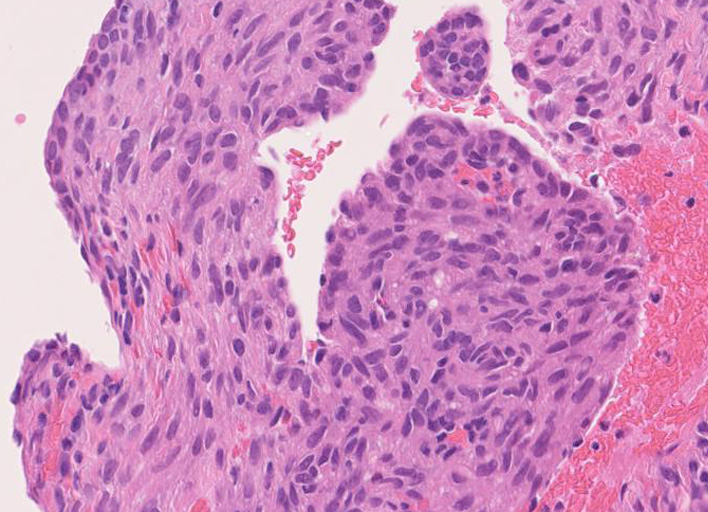

LAMの肺病変

嚢胞周囲または肺血管, リンパ管, 細気管支にそうLAM cellの浸潤, 集簇を特徴とする。LAM cellには2種類が認められ, 小型紡錘形細胞と細胞質の豊富な類上皮様細胞があり, 紡錘型は主に集簇巣の中心に存在し増殖能が高い。 類上皮様LAM cellは辺縁部に多く, 増殖能は低いがHMB45を強く発現している。

LAM cellの免疫染色--SMA, desmin, vimentin(vimentinはいつも陽性とはならない)が陽性となりmuscle lineageであるが典型的な筋細胞と異なり,